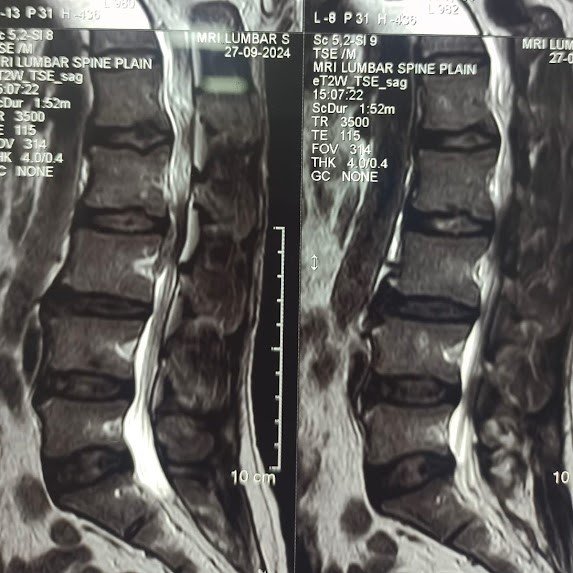

Trustindex verifies that the original source of the review is Google. I visited Dr. Nitish Agarwal for my severe back pain and shoulder issue. He checked my MRI very carefully and gave the perfect diagnosis. Yesterday, he performed the procedure (Root Block and Shoulder Injection), and it was completely painless. He is an expert and targeted the exact nerve point causing the trouble. Very helpful and humble doctor. Highly recommended for anyone with spine problems.Posted onTrustindex verifies that the original source of the review is Google. I was unable to make movement and suffered from right foot drop which is equal to halfway paralysis. Dr. Nitish Agarwal performed very fine microscopic surgery on L3, L4 & L5. After 90 days under his treatment I could go for a walk min. 6 kms a day, I have started my regular activities after 120 days. Thank you so much Dr. Nitish Agarwal sir.Posted onTrustindex verifies that the original source of the review is Google. I was suffering from severe back pain, and Dr. Nitish Agrawal has been extremely supportive throughout my treatment. He listened carefully, explained everything clearly, and guided me very well. His treatment has really helped me recover. He is one of the best spine specialists — highly recommended!Posted onTrustindex verifies that the original source of the review is Google. I had consulted many doctors before Dr Nitish for my mother's spine issue,most recommended complex procedures and surgeries. Fortunately we found Dr Nitish and it has been life changing for my mother,she was in immense pain before the simple surgery he did. It's rare to find a surgeon who explains everything in detail and provides such exceptional care even after the surgery. I Would highly recommend him.Posted onTrustindex verifies that the original source of the review is Google. My mother had sustained a fracture to her right hand wrist and we were worried about her recovery due to age factor. One of our family Doctor referred us to Dr. Nitish Agrawal and we visited Dr. Nitish Sir. Dr. Nitish sir ensured that my mother don't need a surgery and treated her by application of plaster (temporary and then cast-iron or Firm plaster) with certain orthopaedic treatment to hand and prescribed oral medication for ensuring recovery is faster without any surgery. Attaching the photo of xray which shows recovery of wrist bone which has rejoined and we are still continuing treatment to ensure my mother is fully recovered and is fit. Thank you Dr.Nitish Agrawal for your support.Posted onTrustindex verifies that the original source of the review is Google. Hi everyone, myself Samadhan. I was suffering from severe spine pain for a long time, and one of my friends suggested I visit Dr. Nitish Agarwal. Honestly, that was the best advice! Dr. Nitish listened to my problem very patiently, explained the cause in detail, and gave me the right treatment. I started feeling better within a short time. He is very polite, knowledgeable, and truly cares for his patients. I highly recommend Dr. Nitish Agarwal for anyone dealing with spine or back pain. Thank you, doctor, for your excellent treatment and support!Posted onTrustindex verifies that the original source of the review is Google. Dr. Nitish Agrawal is an excellent spine specialist who patiently listens, explains the problem clearly, and provides the best treatment options.Posted onTrustindex verifies that the original source of the review is Google. Dr.Nitish sir is an incredible surgeon. I had excellent results from my recent spine surgery. The entire process, from consultation to recovery, was handled with professionalism and care. The outcome has been life-changing. I highly recommend Dr.Nitish agarwal to anyone in need of a spine surgeon.Posted onTrustindex verifies that the original source of the review is Google. A few months back I took treatment for my back pain from dr. Agarwal sir ...last 7-8 years i was suffering with low back pain,unbale to stand for more than 10 minutes..My low back hurts continuously, and also left leg pain was unbearable....i try every possible way of treatment from various suggestion...After several treatment...one of my relative suggested dr. Nitish Agarwal sirs name then I visited Dr. Nitish Agarwal sir in clinic. He suggested me x ray and MRI. On that basis he advise me caudal Block with root block with facet block for pain management. After block my pain goes with in a week. He advise me regular Physiotherapy at home. Now after regular exercise I am pain Free. Dr. Nitish Agarwal is a good doctor for any spine related problem.... Thank u dr. Agarwal Sir 🙏Posted onTrustindex verifies that the original source of the review is Google. My wife had major infection in neck and lower back. She was bedridden. her legs and hands were weak. Then we admit her under Dr. Nitish Agarwal sir and did MRI. He explained that she is having major infection in cervical and lumbar spine. Due to infection her spinal cord is compressed so she was not able to walk. Then sir did operation for neck and removed infected tissue and spinal cord is freed and put a plate. Her lower back is treated with medicine only. She was given 2 months antibiotics by saline and 5 months oral antibiotics were given. He also advised regular exercise. After 15 days of surgery she started walking with support. Now after 1 year she is completely alright and walking like a normal person. She is regularly doing all her activities. Now she can also travel by 2 wheeler. Thank you to Dr. Nitish Agarwal sir for his expert work in spine. I recommend Dr. Nitish Agarwal for any spine related problem.